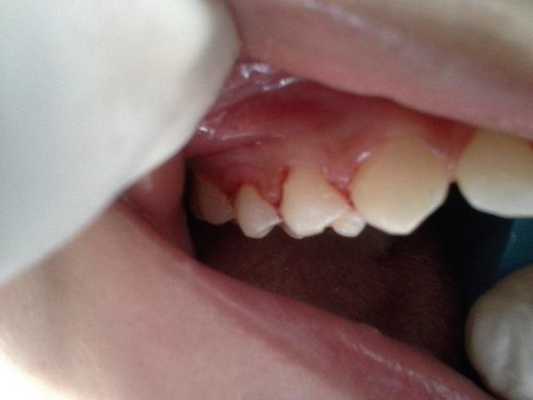

При реализации концепции протокола предоставления медицинской помощи, первоочередной задачей являлось уменьшение периодических приступов пневмонии, что предусматривало использование химиотерапевтических агентов в сочетании с ручным удалением видимого зубного камня (фото 4). Так, непосредственно перед клиническим вмешательством проводилась антибактериальная терапия с использованием 0,12% хлоргексидина, за которой следовала гигиеническая манипуляция удаления зубного камня.

Фото 4: Клиническая картина ротовой полости после лечения.